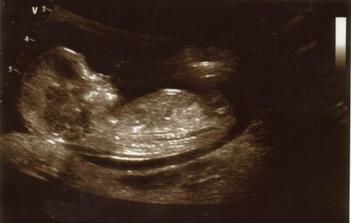

9.2.2009 kontrola u doktora - je tam mimís i se srdíčkem 🙂